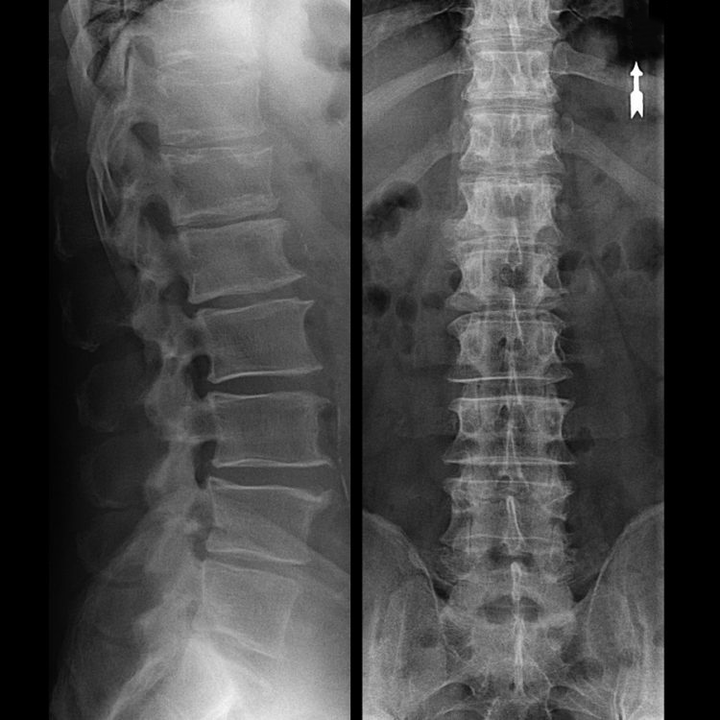

An "X-ray" of the cervical spine, and even with functional tests for flexion and extension, does not show cartilage, because their tissue allows x-rays.Despite this, based on the position of the vertebrae, general conclusions can be drawn about the height of the intervertebral discs, the general correction of the physiological curvature of the neck - lordosis, as well as the presence of marginal growths on the vertebrae with prolonged irritation of their surfaces by fragile and dehydrated intervertebral discs.Functional tests can confirm the diagnosis of instability in the cervical spine.

Since discs can only be seen with CT or MRI, magnetic resonance and X-ray computed tomography are indicated to clarify the internal structure of the cartilage and formations such as protrusions and hernias.Thus, with the help of these methods, an accurate diagnosis is made, and the findings of tomography are an indication and even a topical guide for surgical treatment of hernia in the department of neurosurgery.

- You can regularly do at least a two-view lumbar spine X-ray, or an MRI, to know if the hernia, if any, is progressing;